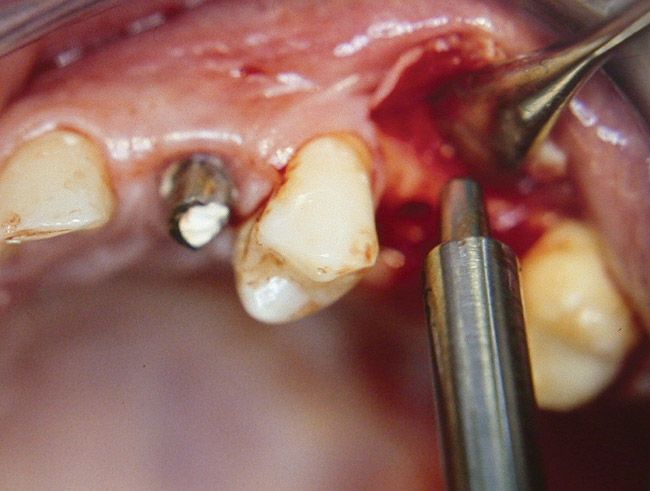

At the time of surgery, the tooth was extracted without harvesting any mucosal flap because the implant site was prepared by means of a pilot drill bur (Figure 13) and alternating osteotomes (Figure 14A and Figure 14B). The implant was positioned and showed primary stability. The implant was loaded 2 days after surgery. Then, splinted PFM crowns supported by custom gold abutments were delivered. At 6 months posttreatment, the radiograph revealed no bone resorption and the clinical result was optimal (Figure 15A and Figure 15B).

Figure 14A and Figure 14B Alternating osteotomes were used to prepare the implant site.

Figure 14a  Alternating osteotomes were used to prepare the implant site.

Figure 14a

Figure 14b  Alternating osteotomes were used to prepare the implant site.

Figure 14b